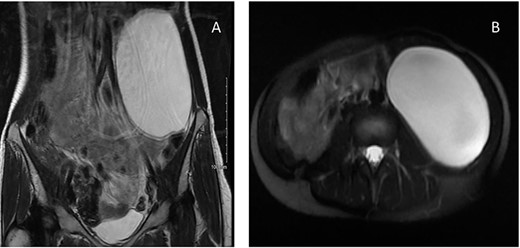

In order to characterize the lesion further, magnetic resonance scan was organized. This demonstrated a 10 × 7 × 15 cm cystic lesion in the left flank between Gerota’s fascia and the descending colon, confirming its retroperitoneal location. The fluid within the lesion was described as simple, with homogenously high T2 and low T1 signals. A possible thin septation was seen within the superior aspect of the cyst, but there was no evidence of any soft tissue component. There was no enhancement within the cyst or its wall (Fig. 2). The most likely differentials at this stage included a lymphangioma or mucinous cystadenoma.

MRI of a 32-year-old woman presenting with chronic abdominal pain and a mass in left iliac fossa. (A) Axial T2-weighted fat-saturated images demonstrate a 10 × 7 × 15 cm cystic lesion in the left flank between Gerota’s fascia and the descending colon. (B) Coronal T2-weighted images confirm the absence of internal nodularity or invasive features.